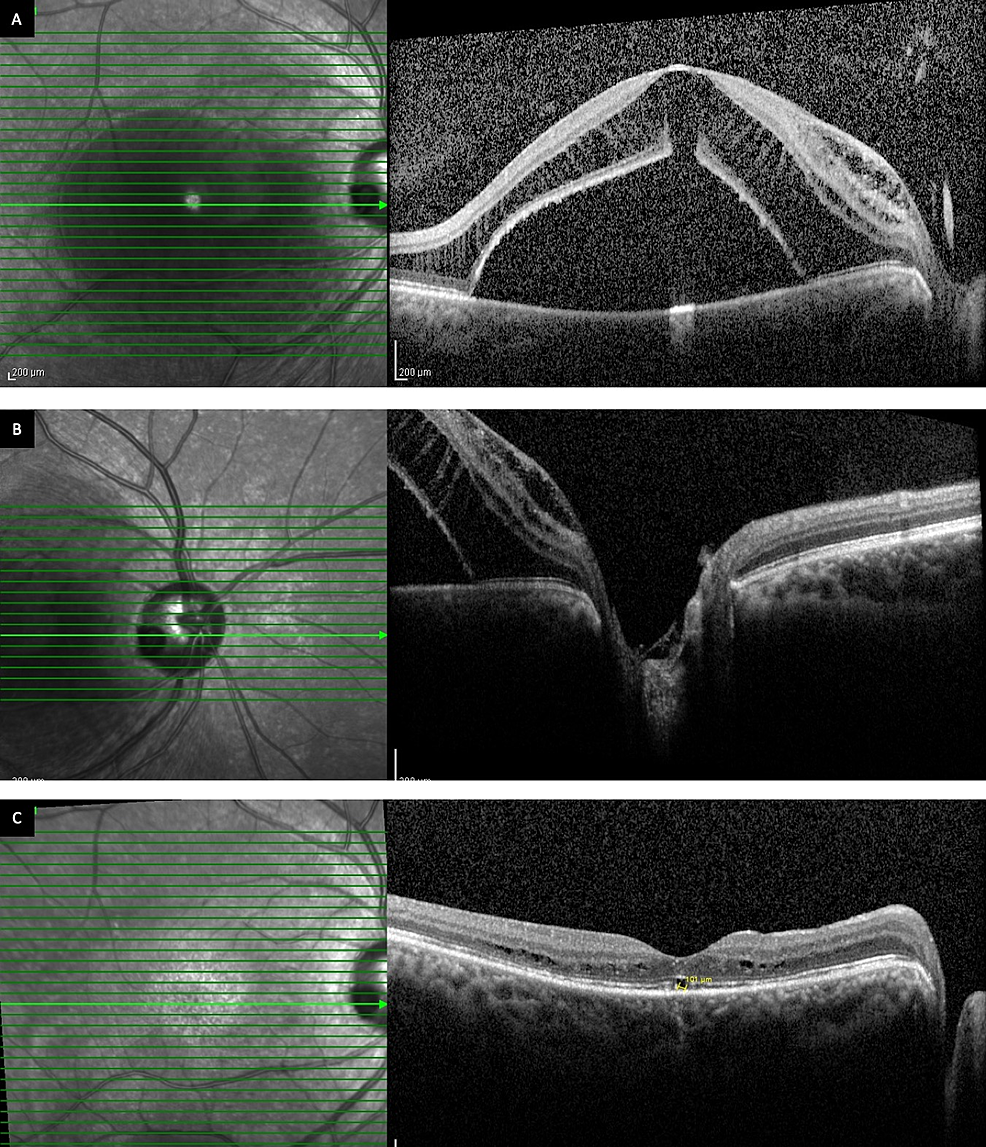

Preoperative OCT shows an optic disc pit maculopathy (a). 1 and 3 Optic Disc Maculopathy It’s been proposed that optic disc pit maculopathy begins with splitting within the inner retinal layers, similar to macular schisis, and progresses to serous macular detachment following. Optic disk pit (odp) is a rare congenital abnormality of the optic nerve head. A look at diagnosis and management of optic disc pits, a condition that can lead to optic disc maculopathy. Optic Disc Maculopathy.

From jmedicalcasereports.biomedcentral.com